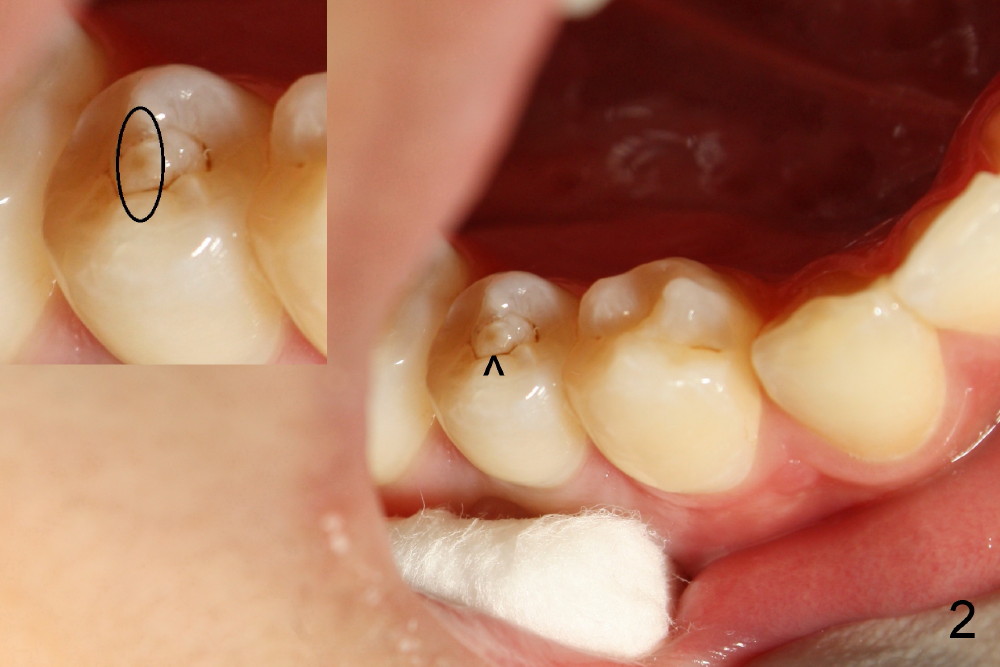

上集发表时,还没有见到病人,这集回答卢红医师疑问(下面)。今天病人来诊所诊治,他没有任何症状,右下五号牙根尖瘘道(图一箭头)是以前牙齿矫正医生发现的,咬合面中央隆起(图二箭头),后者中心好像有个小开口。对侧仿佛没有同样病变(图三*:左下五)。按照方柄忠大夫建议,根管治疗前做活力测试(Endo Ice):右下五的确死髓,有轻度扣痛。

治疗前告诉病人,如果治疗后瘘道不消失,可能需要进一步治疗(根尖切除术)。根管开口(Access)如图二插图表示,唯一不理解的是这个牙齿只有一个根管,似乎偏向颊侧,扩大针尽量往舌侧拉,颊舌侧之间好像有狭部感觉(Isthmus)。Apex Locator运转正常,说明根尖关闭。预先弯曲扩大针:10-20号,然后使用40/.06 rotary file,太容易达到根尖,所以逐步使用扩大针治七十号,但是逐渐失去working length (WL),最后七十号牙胶尖插不到根尖(图四(箭头:根尖阴影)),而40/.06牙胶尖在有冲洗液下容易达到WL,接触(Binding)不够紧密,好像再大一号扩大针(四十五号)就达到不了WL。由于时间问题,使用AH26 Plus Paste,主牙胶尖40/.06,以及medium and fine medium accessory gutta percha(各一根)完成充填(图五),最后树脂充填,不准备做牙冠,观察。